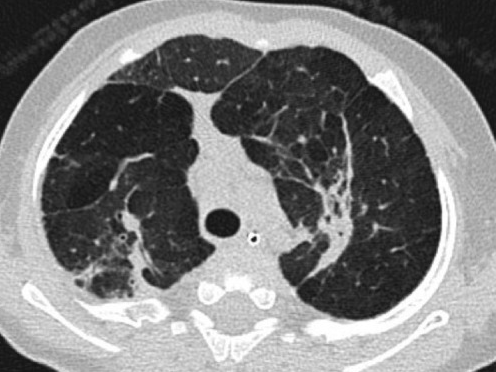

RX

- Zones d’hyperinflation et d’atélectasies

- Epaississement interstitiel (exsudat d’éosinophile)